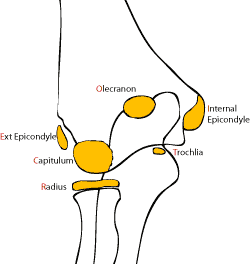

Doğumda dirsek eklemi tamamen kıkırdaktır ve radyografilerde bu kıkırdak alana bağlı olarak geniş radyolüsent bir alan görülür. Büyümeyle birlikte kemik dirseği oluşturacak ikincil kemikleşme noktaları ortaya çıkar. Düzgün radyolojik değerlendirmenin yapılabilmesi için bu kemikleşme noktalarının anatomik yapısı ve gelişiminin iyi bilinmesi gereklidir.

Bu noktaların ortaya çıkma zamanı tahmin edilebilir ancak hastadan hastaya, yaşa, cinsiyete, gelişime göre farklılık gösterebileceği unutulmamalıdır. Karşı taraftaki dirsekle karşılaştırılması patolojik görünüm ya da yapısal farklılığın ayırt edilmesinde yardımcı olur. Bu kemikleşme merkezlerinden ilk ortaya çıkanı Kapitulumdur. Ortaya çıkma sırasına göre “CRITOE” kısaltması kullanılabilir. Kapitulum hariç bu merkezler kızlarda erkeklere göre daha erken görülmektedir.